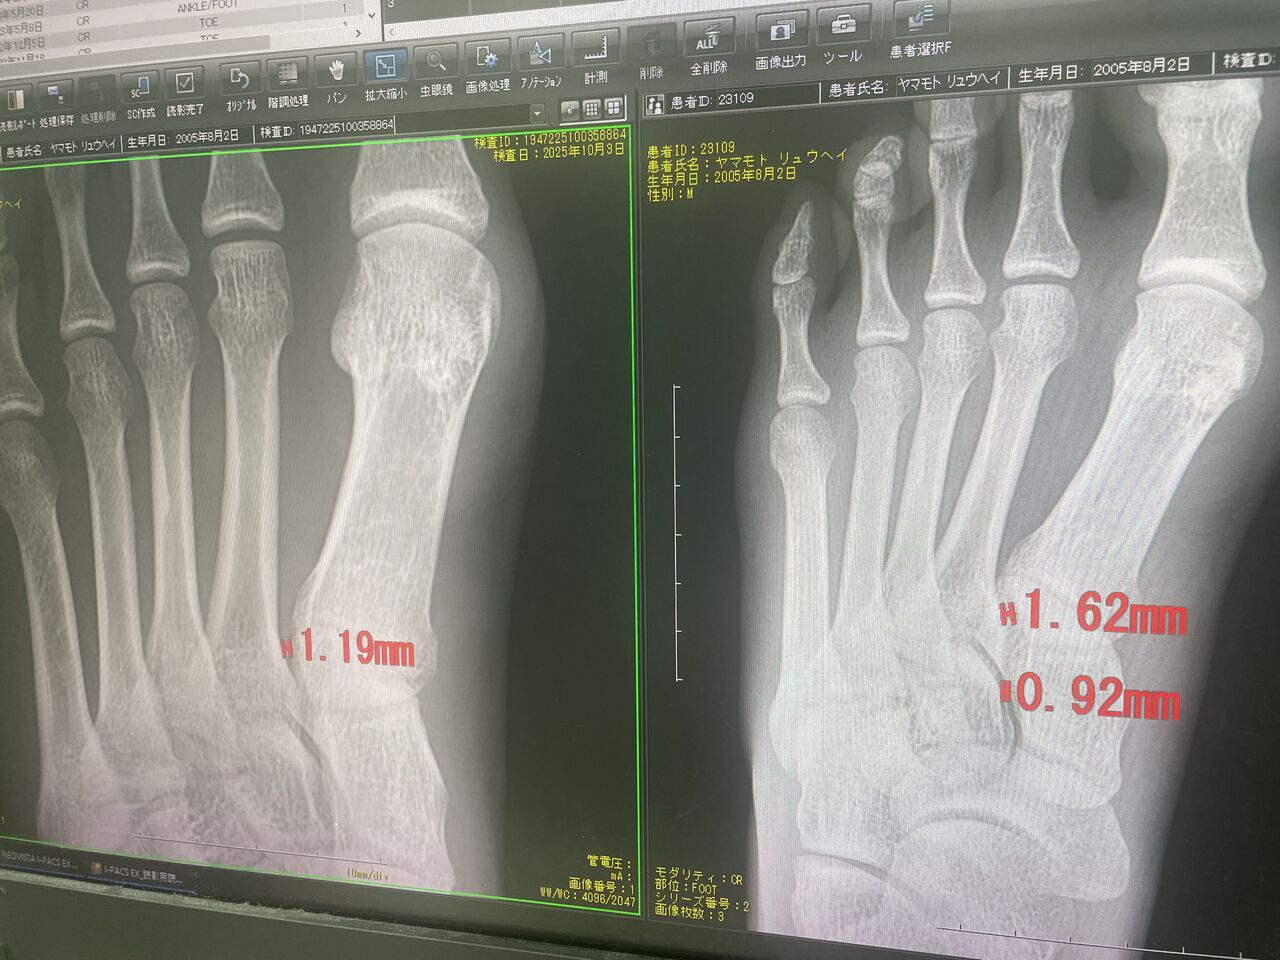

2025年10月04日 一般患者様みながら、連日アスリート 全日本モトクロス選手権、チャンピオン 残り2戦 何とか怪我に負けずに 入賞させよう、 今年は5連覇がかかっておりますので どうしても直していきたいと思います プロキックボクサー 回し蹴りで、骨折 フレックスサインあるも これは保存的治療で直します . カテゴリなしの他の記事 < 前の記事次の記事 >